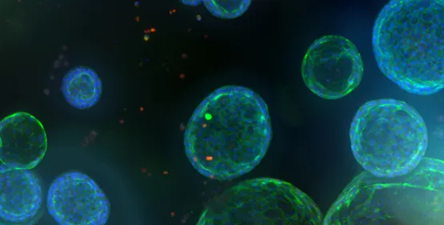

Image Credit: Molecular Devices UK Ltd